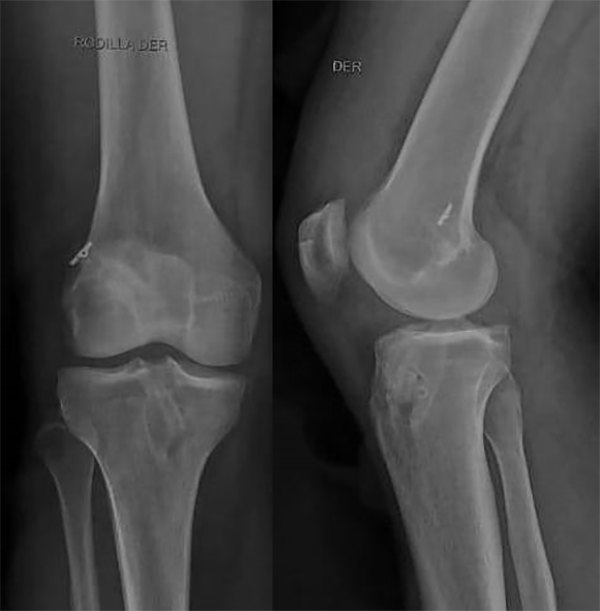

Se realizó control radiográfico postoperatorio, y se constató correcta posición de túneles y material de fijación. Rótula en buen estado (fig. 8).

Figura 8: Rx postoperatoria de rodilla derecha. Rótula, túneles e implantes de fijación en buen estado.